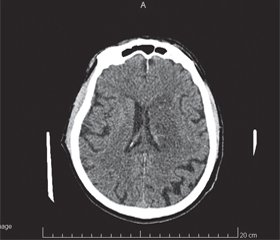

Інструментальні обстеження. Електрокардіографія (12.07.19): нормальне положення ЕВС. ЧСС — 72 уд/хв. Часта передсердна екстрасистолія. Виражені метаболічні, склеротичні зміни міокарда. Рентгенографія органів грудної клітки (12.07.19): легеневі поля без інфільтративних змін. Корені структурні. Серце в межах норми. СКТ головного мозку (12.07.19, 11:33): на серії томограм головного мозку ознаки ДЕП, атрофічного процесу головного мозку (рис. 1).

Через 2,5 години після ТЛТ в КМЛ повторно проводяться СКТ головного мозку (рис. 2) та селективна церебральна ангіографія.

Через 6,5 години контроль СКТ фіксує геморагічні трансформації в ділянці ішемії. Геморагічна трансформація відбулася внаслідок тромболітичної терапії (застосування актилізе), ангіографії, екстракції тромбу, стентування субоклюзії устя ЛВСА (рис. 3). Через 19 днів лікування на СКТ — резорбція геморагічної трансформації (рис. 4).